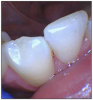

Canines tend to show the first visual signs of bruxism because the anatomy of a canine is longer and more pointed than other tooth types. Wear facets or flat canines are obvious visual signs of grinding (Figure 2). As the canines become shorter and become in line with the occlusal line of the premolars, the force is then shared with the rest of the molars (Figure 3). Signs of attrition on molars start with the cusps flattening out and can even wear through to the dentin.37

Figure 2. Facial surface exhibiting flattened, smooth, polished enamel wear on tooth #23.

Figure 2

Figure 3. Lingual and occlusal surfaces exhibiting polished wear on tooth #5.

Figure 3